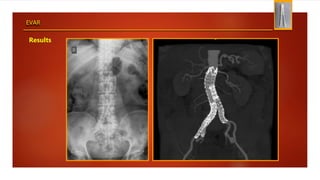

Results

EVAR